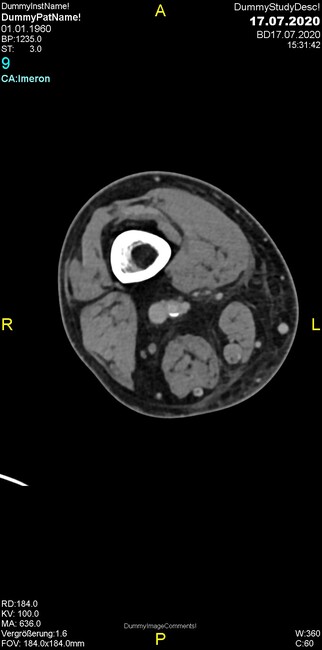

Um welche Modalitäten handelt es sich?

- Röntgen p.a. und lateral, CT coronar Knochenfenster, CT axial Weichgewebsfenster

Was fällt in der CT im Knochenfenster auf?

- Mediale Gelenkspaltverschmälerung

- Dezente Erosion der fibulären Kortikalis

- Frakturspalt der lateralen Tibiametaphyse

- Weichgewebskalzifikationen lateral angrenzend an den Gelenkspalt

- Osteolyse der Tibiametaphyse unter Beteiligung der Kortikalis